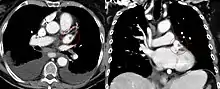

The atrium (Latin: ātrium, lit. 'entry hall'; pl.: atria) is one of the two upper chambers in the heart that receives blood from the circulatory system. The blood in the atria is pumped into the heart ventricles through the atrioventricular mitral and tricuspid heart valves.

There are two atria in the human heart – the left atrium receives blood from the pulmonary circulation, and the right atrium receives blood from the venae cavae of the systemic circulation. During the cardiac cycle the atria receive blood while relaxed in diastole, then contract in systole to move blood to the ventricles. Each atrium is roughly cube-shaped except for an ear-shaped projection called an atrial appendage, previously known as an auricle. All animals with a closed circulatory system have at least one atrium.